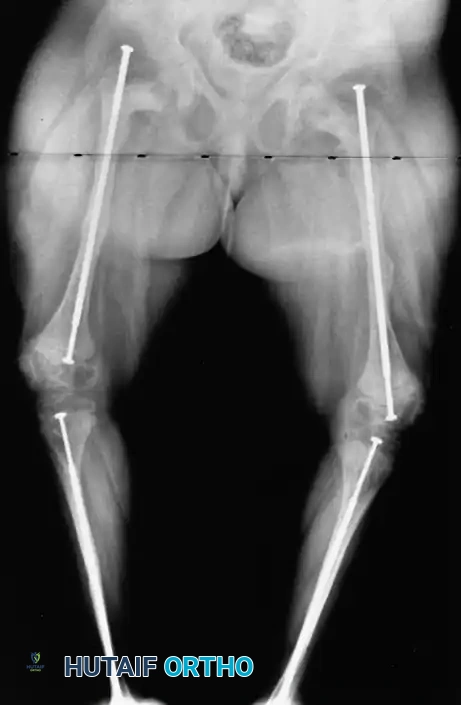

Image

Preoperative radiographic assessment demonstrating severe bowing and osteopenia characteristic of osteogenesis imperfecta, necessitating comprehensive surgical planning.